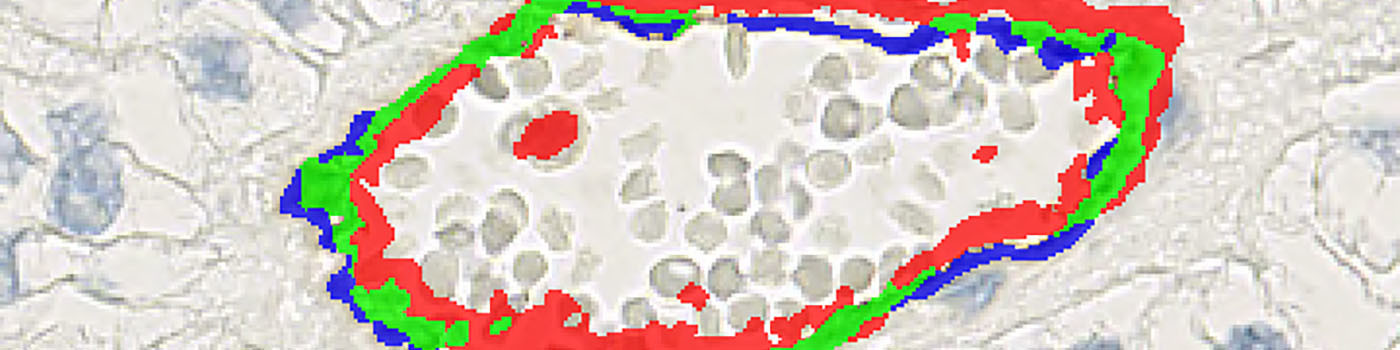

From a TMA block, sequential slides were obtained and each slide was stained with either CD31 or CD34 (see FIGURE 1). Using the patented Autodisector technology, the two sequential slides can be overlaid (see FIGURE 2) and each TMA core-pair is automatically aligned at a high magnification, cell-to-cell level, to facilitate the detection of overlapping positive stain between the two slides (see FIGURE 7).

Based on a DAB color deconvolution, (see FIGURE 5), the positive stain areas are identified as areas where the stain density is higher than a certain threshold. This leads to a segmentation of the image using three labels:

Overlap Pos Stain: Areas where the stain density is high enough for both CD31 and CD34.

CD31 Positive: Areas where only CD31 positivity is present.

CD34 Positive: Areas where only CD34 positivity is present.

These three categories are labeled in green, blue, and red respectively, (see FIGURE 6).